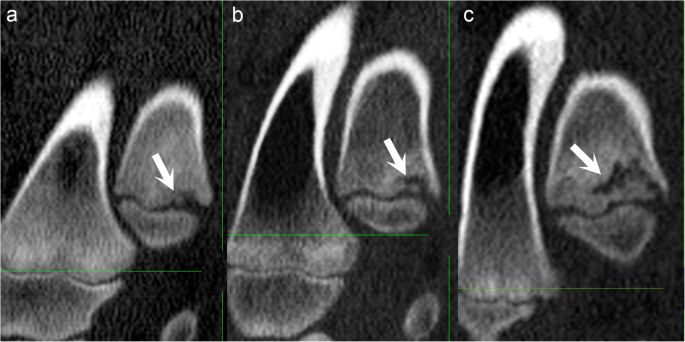

Secondary reparative ossification. All images are in the sagittal plane. Proximal is to the top, distal is to the bottom, cranial is to the left and caudal is to the right of each image. a Pig 16, interval 6, left distal ulna. There is a mineral hyperdense focus (arrow), interpreted as a separate centre of reparative ossification, at the transition between the lesion and the physis. b Pig 18, interval 4, left distal ulna. There is a linear hyperdensity (arrow) that is connected with the metaphyseal-side ossification front. c Pig 14, interval 7, left distal ulna. There is a linear hyperdensity (arrow) that extends horizontally into the defect, causing it to appear reverse-C-shaped